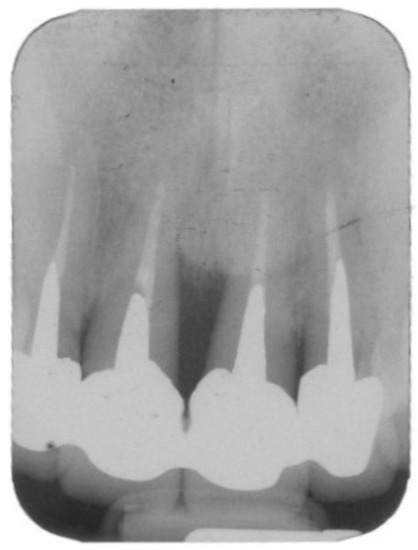

Figure 1.

Periapical radiographs of a 37-year-old nonsmoker woman with hopeless 12–22 teeth due to severe bone loss (patient# 17).